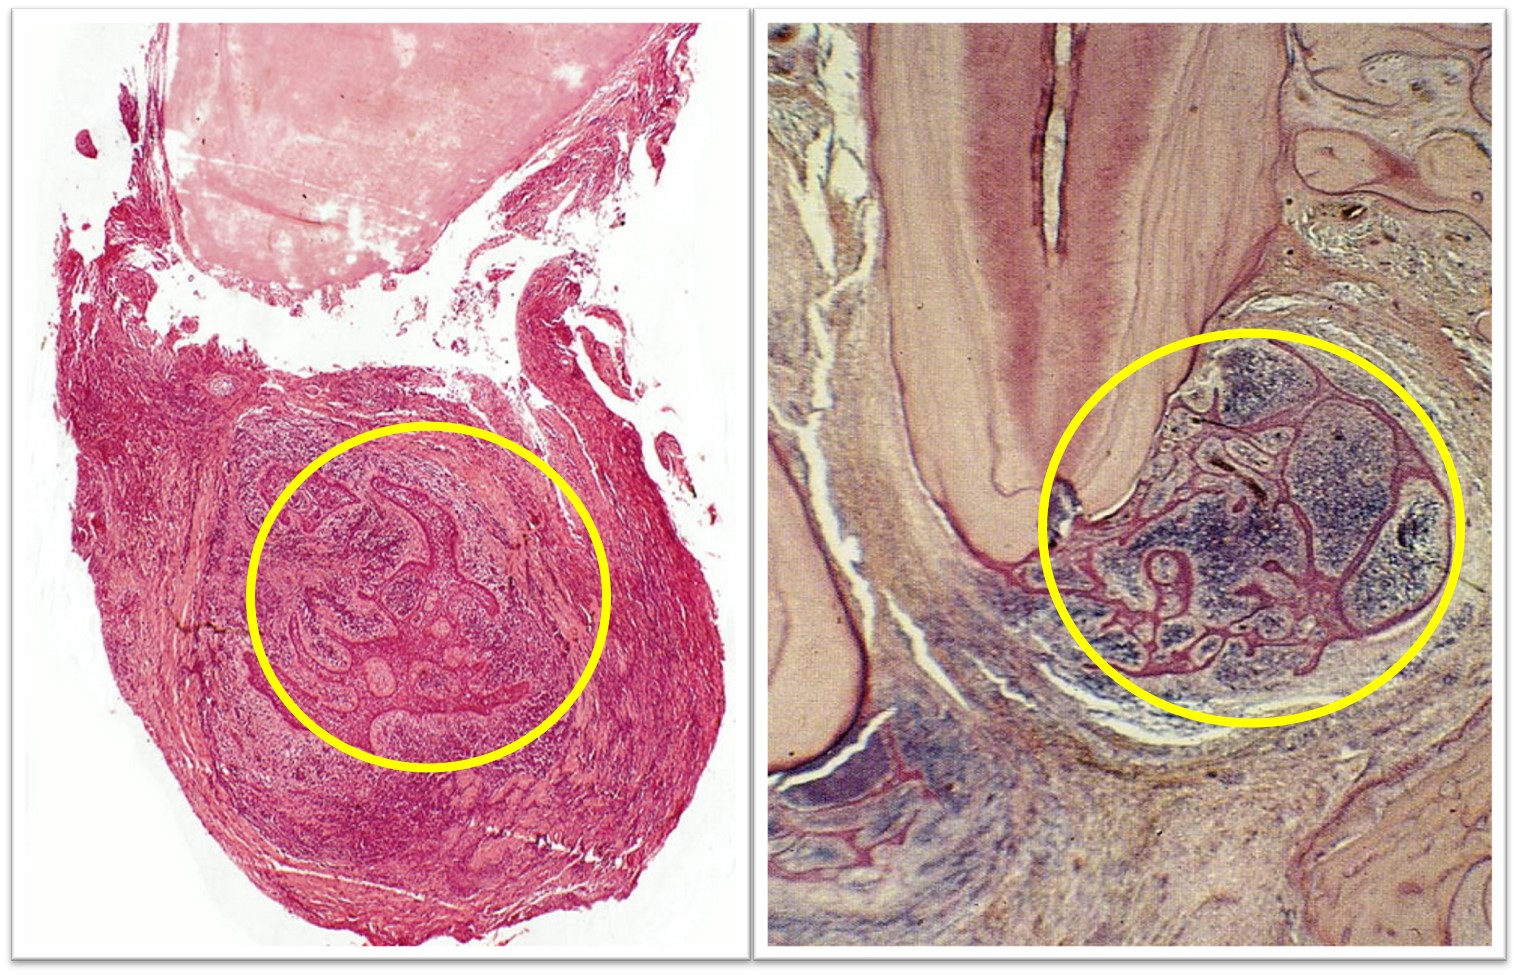

有时根尖周肉芽肿内可见增生上皮团或上皮条索相互交织成网状(图9.2-3)。

图9.2-3 上皮性根尖周肉芽肿

★根尖周肉芽肿的上皮来源(图9.2-4):Malassez上皮剩余;经窦道口长入的口腔黏膜上皮或皮肤;牙周袋上皮;呼吸道上皮。

图9.2-4 上皮性根尖周肉芽肿的上皮来源